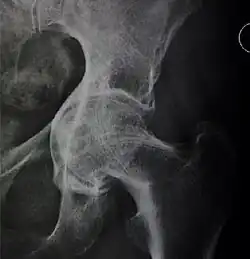

![Hip dysplasia.[3]](./_assets_/X-ray_of_measurements_in_hip_dysplasia.jpg)